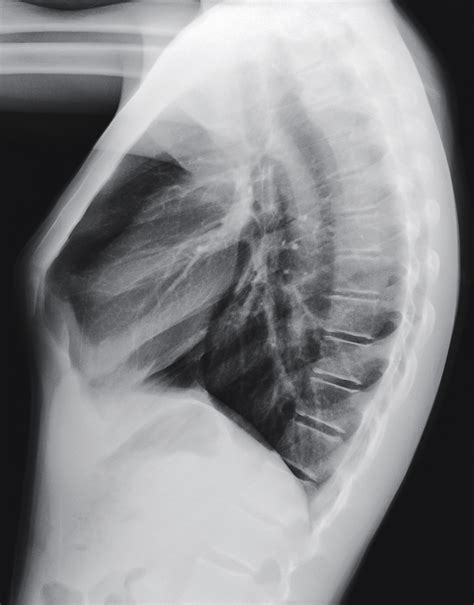

A normal chest X-ray shows a clear and symmetrical image of the lungs, heart, and chest wall. The lungs should appear dark and free of any abnormalities, while the heart should be of normal size and shape. The chest wall and ribs should also appear normal, with no signs of fractures or other injuries. It is essential to note that a normal chest X-ray does not necessarily rule out all possible health issues, as some conditions may not be visible on an X-ray.

Here are five ways to interpret a normal chest X-ray: * Lung Fields: The lung fields should be clear and free of any abnormalities, such as nodules, masses, or infiltrates. The lungs should also be of equal size and shape. * Heart Size and Shape: The heart should be of normal size and shape, with no signs of enlargement or abnormality. The cardiothoracic ratio, which is the ratio of the heart size to the chest size, should be within normal limits. * Chest Wall and Ribs: The chest wall and ribs should appear normal, with no signs of fractures, deformities, or other injuries. * Diaphragm and Mediastinum: The diaphragm and mediastinum should appear normal, with no signs of abnormalities, such as masses or infiltrates. * Pleura and Airways: The pleura and airways should appear normal, with no signs of abnormalities, such as pleural effusions or airway diseases.